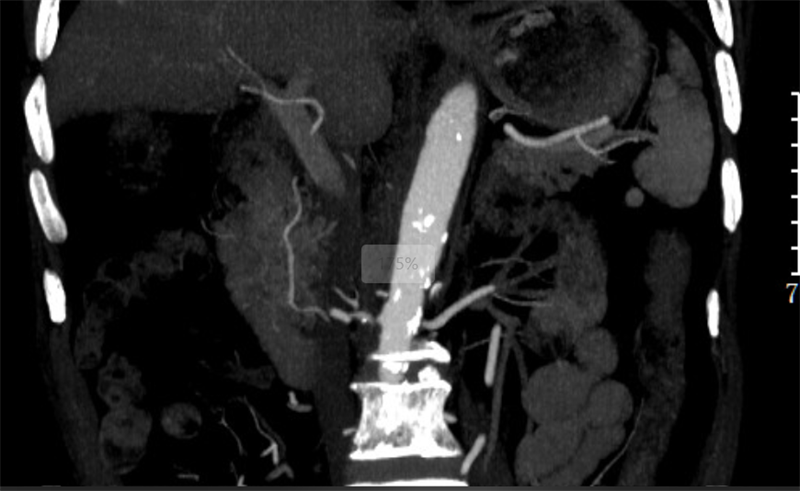

在内分泌科医护人员的精心治疗下,杨先生的血糖逐渐稳定下来,可血压却依旧居高不下。经过增强CT检查发现,杨先生双肾动脉出现了斑块,管腔已经重度狭窄。于是,内分泌科邀请介入医学科专家前来会诊。经过会诊,杨先生被确诊为:双肾动脉狭窄、高血压急症、慢性肾衰竭(伴有肾性贫血、代谢性酸中毒以及肾性高血压)。

| 术前CT |